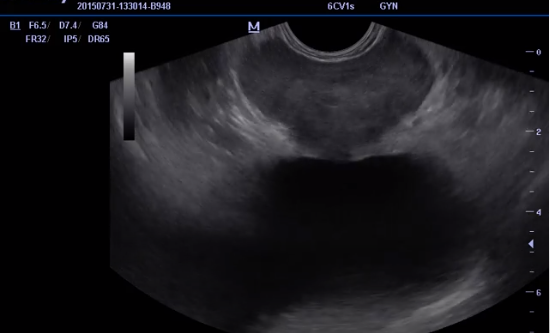

До назначения лечения была проведена ТРУЗИ (Трансректальное ультразвуковое исследование) диагностика простаты органов, а также назначен анализ: бактериальный посев секрета простаты с определением чувствительности к антибиотикам, секрет предстательной железы нативно и по Гр.

-2

В ходе ТРУЗИ выявлены эхографические признаки хронического простатита (неоднородность структуры органа, мелкие кальцификаты, а также признаки гипертрофии предстательной железы (ДГПЖ)). В анализе на бакпосев секрета простаты выявлен Enterococcus spp 10^4, Escherichia coli 10^4, анализ секрета простаты нативно L до 30 в поле зрения.